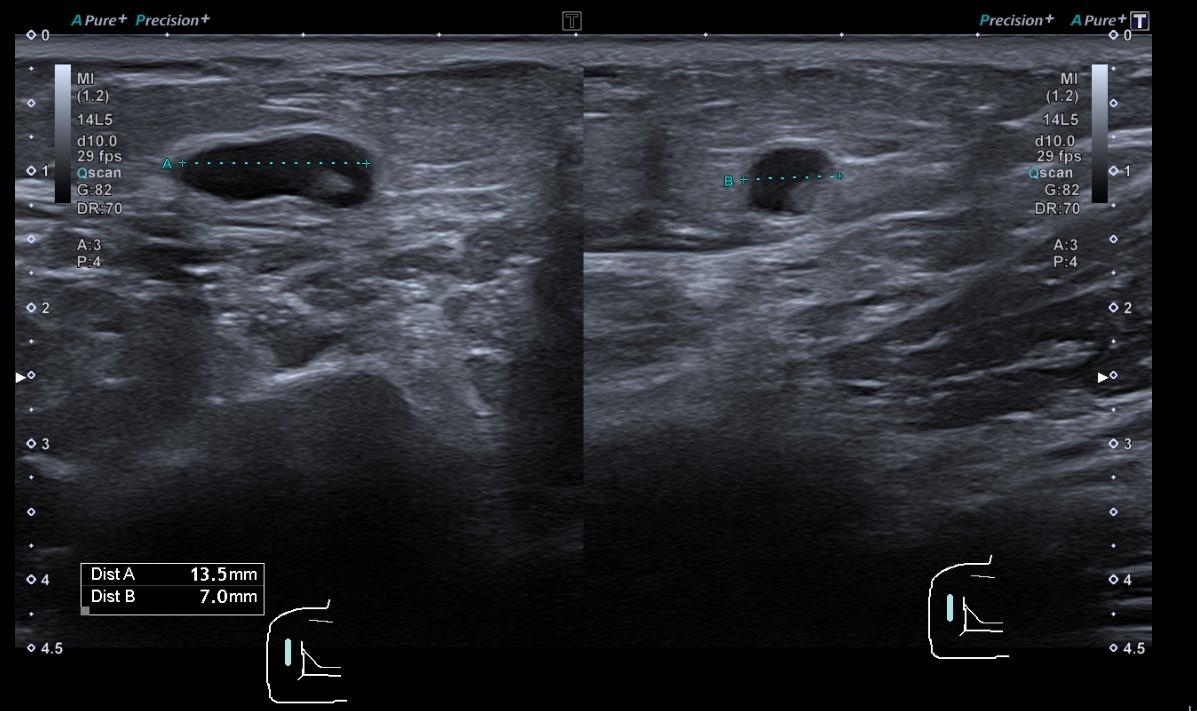

Descripción de los hallazgos ecográficos: formación nodular, isoecoica, de morfología ovalada y bodes delimitados, de un tamaño máximo de 40 x 31 x 12 mm, sugestiva de lipoma subcutáneo. En su interior, muestra dos pequeñas áreas de aspecto quistico, de 7 y 13 mm, sugestivas de áreas de necrosis grasa.

Lipoma con presencia de signos de necrosis grasa en su interior, como probable origen del dolor.